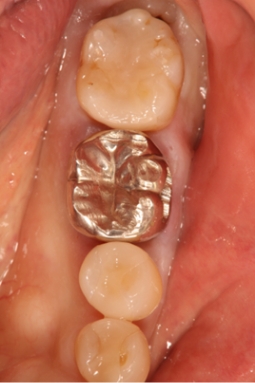

銀歯の下の歯は唾液の侵入によって黒変し、虫歯も生じ歯根破折を起こしている。

特に銀歯は金銀パラジウム合金が口の中で溶けてアレルゲンとして全身に作用し、種々のトラブルを引き起こすことが明らかにされています。